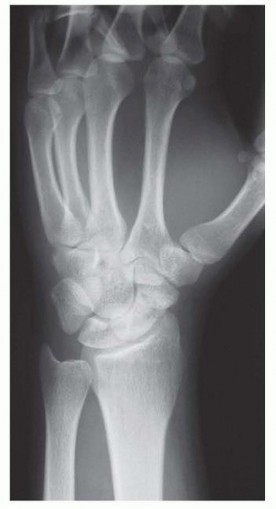

Thorough preoperative planning is what separates an adequate surgeon from a master surgeon. The evaluation begins with a rigorous imaging protocol. Standard posteroanterior (PA), lateral, and specialized scaphoid views (45- and 60-degree pronated oblique views) are mandatory to assess the fracture orientation, degree of displacement, and the presence of any early degenerative spurring at the radial styloid. However, plain radiographs are insufficient for precise surgical templating. A high-resolution Computed Tomography (CT) scan, reformatted in the true sagittal and coronal planes of the scaphoid, is the gold standard. The CT scan allows the surgeon to accurately measure the volumetric bone void, calculate the exact lateral intrascaphoid angle, and template the required dimensions of the corticocancellous wedge graft needed to restore anatomical length.

Furthermore, assessing the vascular status of the proximal pole is a critical preoperative step. While intraoperative assessment of bleeding bone is the ultimate test, a preoperative Magnetic Resonance Imaging (MRI) scan without and with intravenous gadolinium contrast provides invaluable predictive data. A proximal pole that enhances with contrast indicates viable intraosseous microcirculation, validating the plan for a non-vascularized volar wedge graft. Conversely, a dark, non-enhancing proximal pole on T1-weighted fat-suppressed contrast images signals avascular necrosis, prompting a shift in the surgical plan toward a vascularized bone graft. The MRI is also useful for ruling out concomitant soft tissue injuries, such as tears of the scapholunate interosseous ligament or triangular fibrocartilage complex (TFCC).